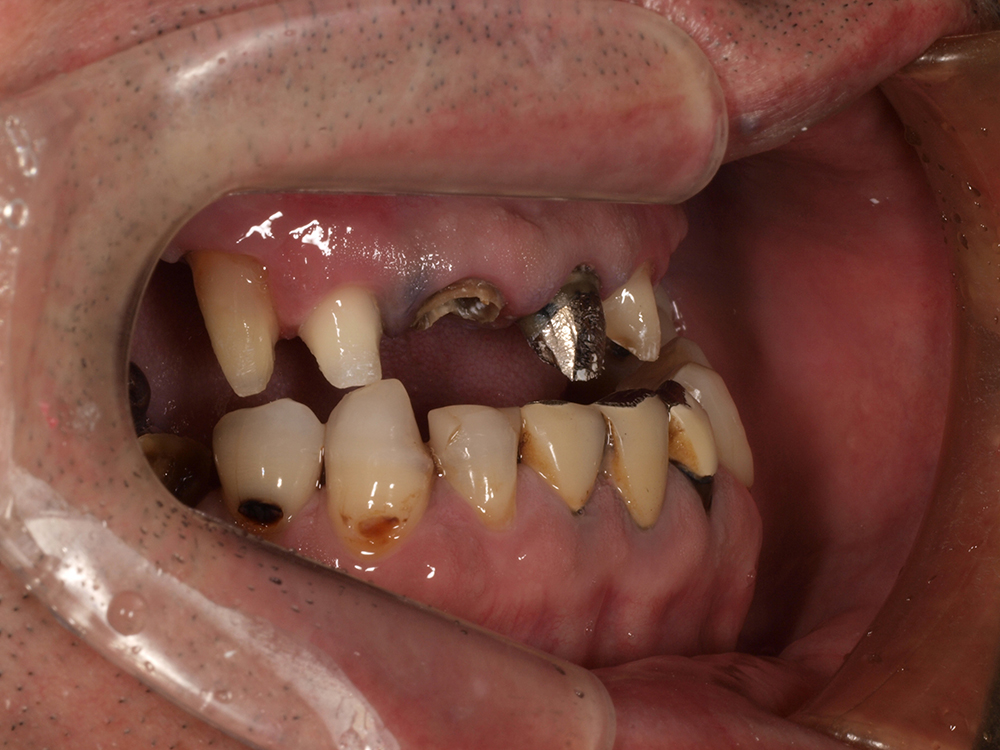

53歳 男性

- 主訴

- 全然噛めない。上の歯が取れてきた

- 処置内容

- 上顎:8本 下顎:2本

- 治療費用

- 上顎:約320万円(税込)、下顎:約160万円(税込)

- 治療期間

-

上顎:1年(仮歯まで8か月)

下顎:8か月(仮歯まで5か月)

- リスク

- 上部構造物、仮歯の破折、術後の腫れ(3日)、人工歯根脱落リスクがあります